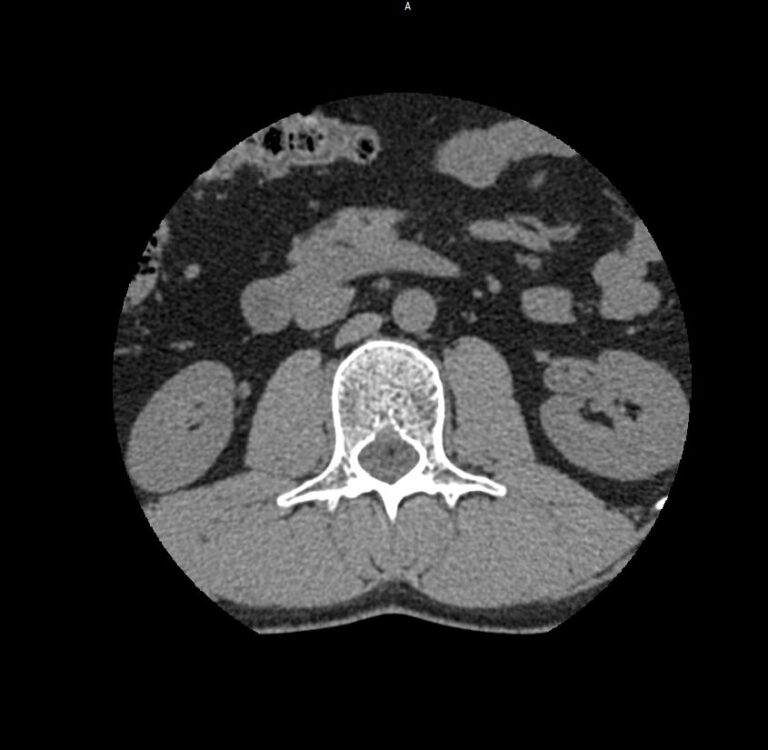

Мультиспиральная компьютерная томография является наиболее точным и информативным методом диагностики различных заболеваний позвоночника и, в частности, пояснично-крестцового отдела. Сканирование проводится при помощи рентгеновского излучения, в результате чего получают серию послойных изображений пояснично-крестцового отдела позвоночника.

В медицинских центрах «Доступная медицина» обследование пояснично-крестцового отдела позвоночника осуществляется на современных мультиспиральных компьютерных томографах последнего поколения TOSHIBA AQUILION в модификациях, позволяющих выполнять одномоментно 64 и 128 срезов анатомической зоны для получения снимков высокого разрешения. Послойное сканирование исследуемой области проводится с минимальной толщиной среза от 0,5 мм, что обеспечивает получение изображений органов в мельчайших подробностях.

Инновационные компьютерные приложения позволяют построить 3D-модель исследуемого органа, обеспечивая детальную визуализацию строения внутренних структур позвонков, хрящевых элементов, кровеносных сосудов и окружающих тканей.

- нет ли грыж (протрузий, экструзий), и если есть – где они находятся, на сколько миллиметров выступают в просвет позвоночного канала, какие анатомические структуры сдавливают;